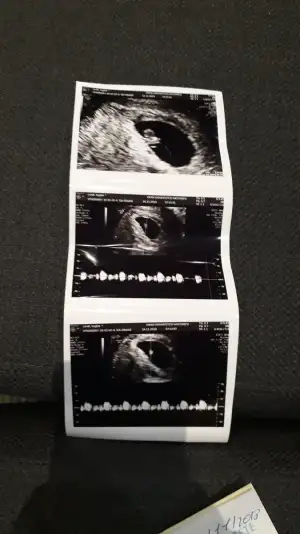

Kalp atışını duyduk çok şükür sata uyumlu![]()